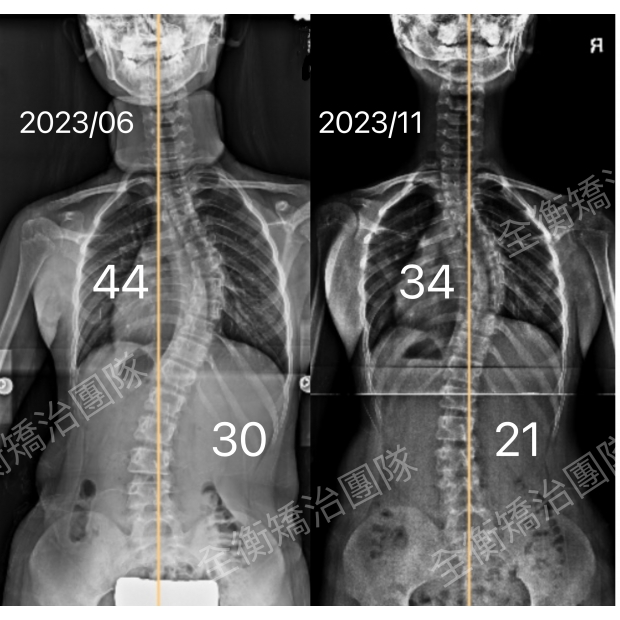

來診後,經醫師檢查發現胸彎已達34度,腰彎28度,由於正值青春快速成長期,惡化風險100%。

為了預防惡化並爭取改善,她開始積極接受專業的側彎矯正運動治療,並認真穿戴施羅斯側彎背架。

僅僅3個月後,女孩的胸主彎從34度改善至17度,進步50% 。